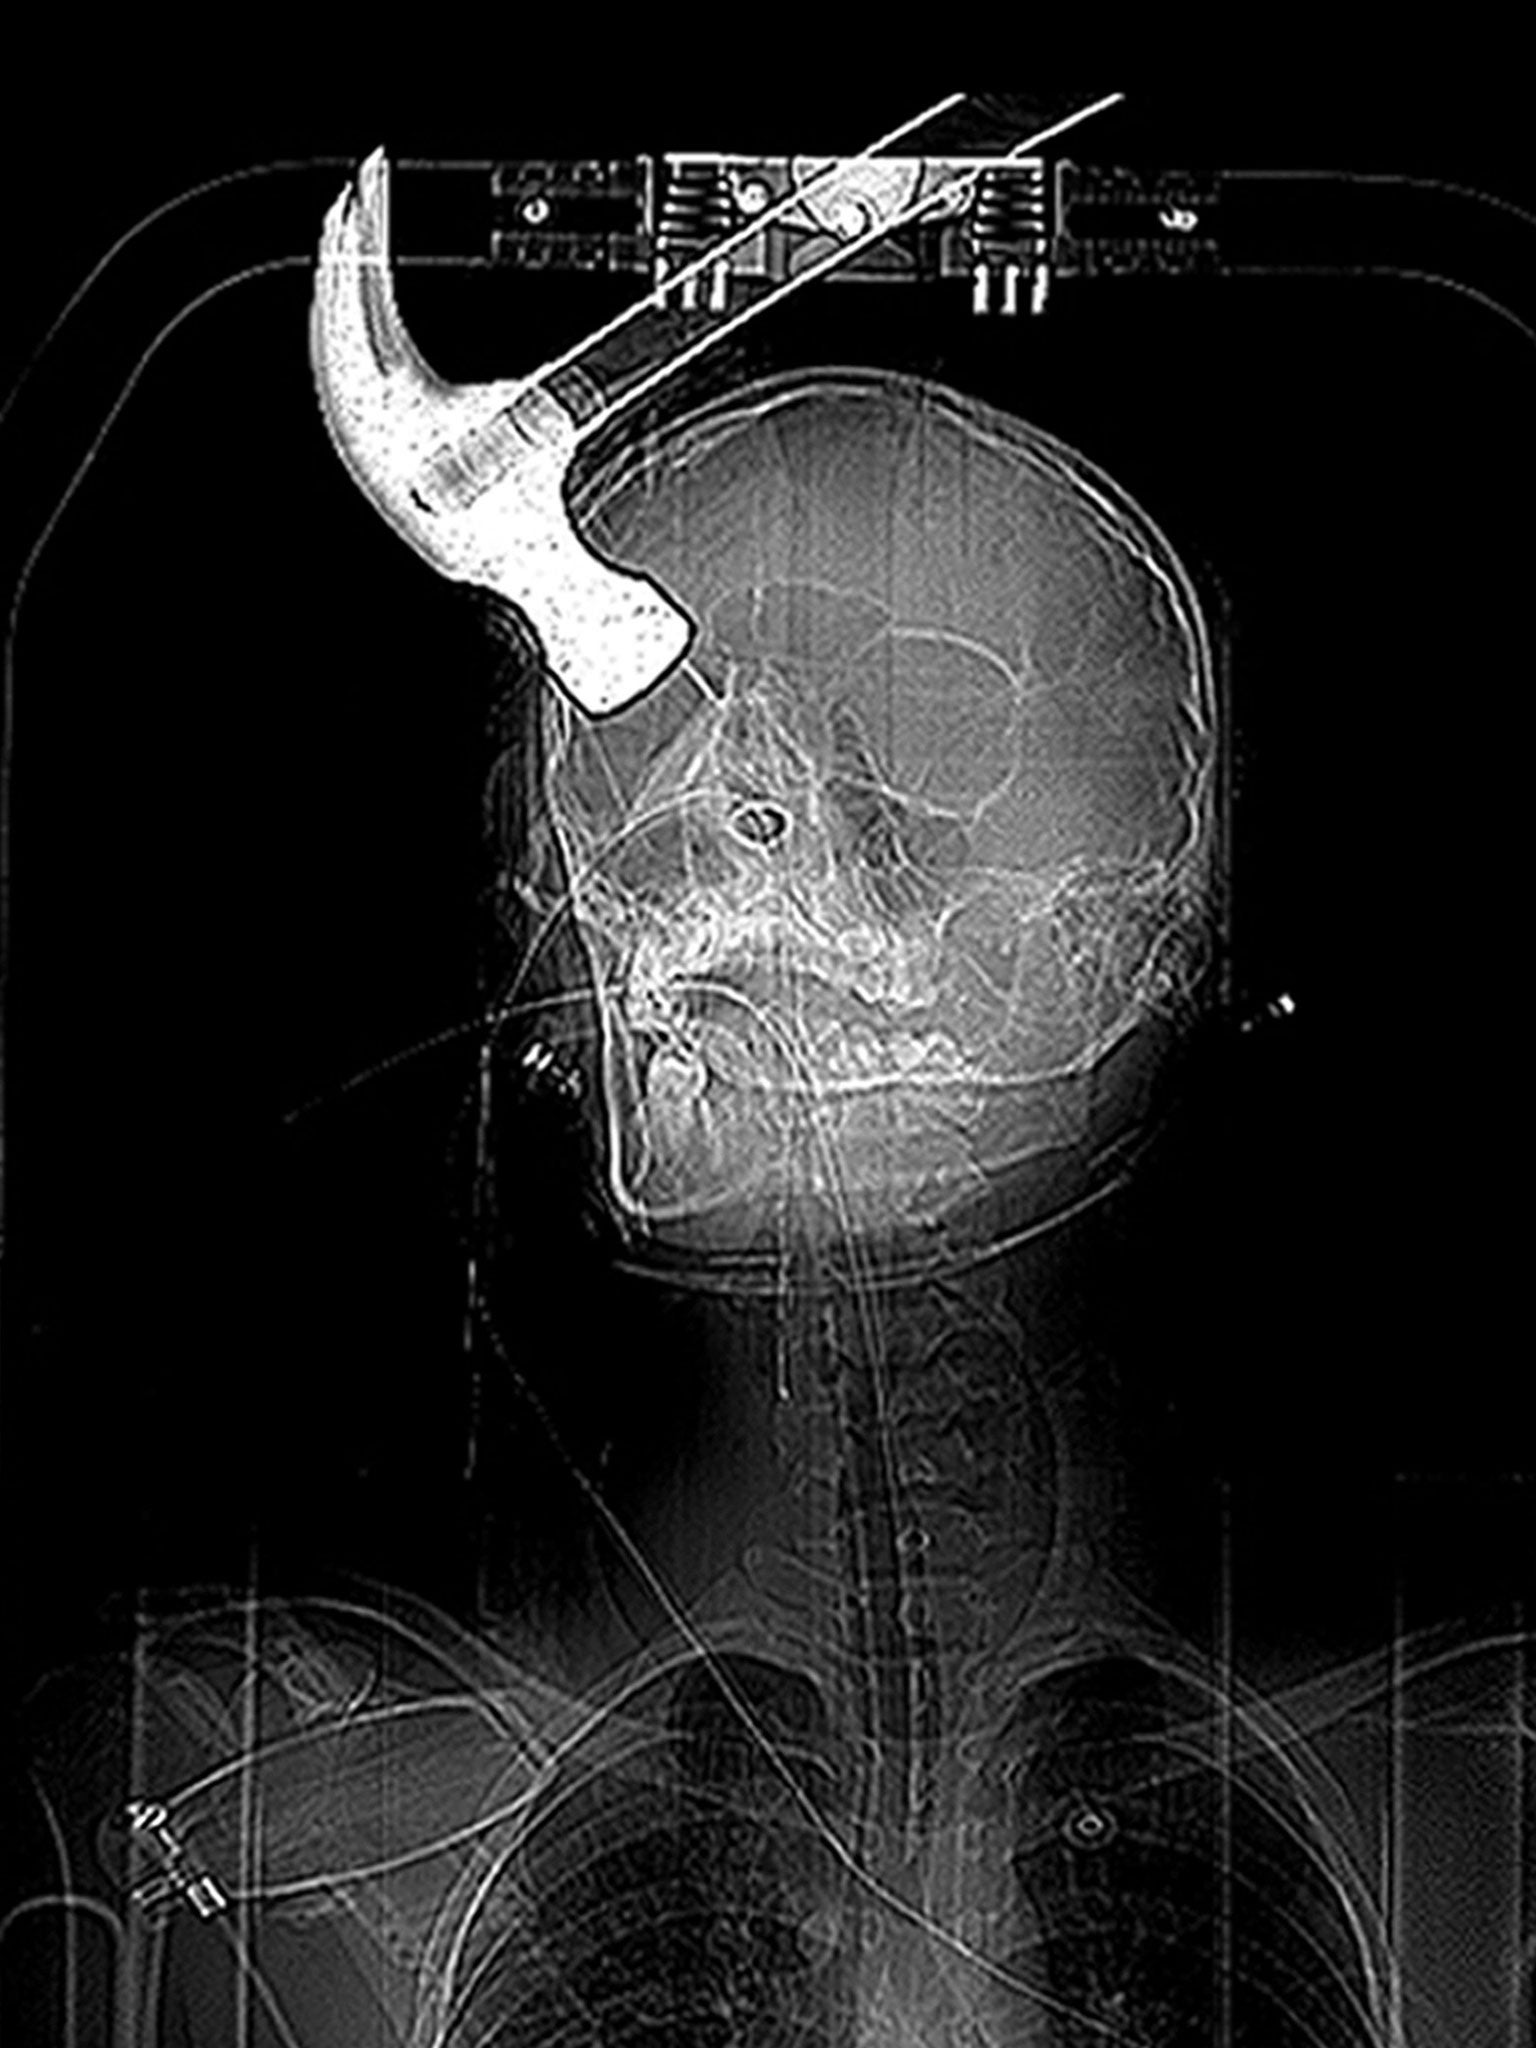

Mr Huntley was found with a hammer embedded into skull

Kent Police went to the flat in Athelstan Road, Cliftonville, and found Mr Huntley on a blood-splattered inflatable air bed still alive but with the claw hammer firmly embedded in his head.

Mr Huntley, who was 18 at the time, was taken to hospital where he was treated for a depressed skull fracture and a penetrating brain injury. A chunk of his skull was removed following the homophobic attack. He now suffers from epilepsy and his body movement has been affected, prosecutor Philip Bennetts QC told the court.